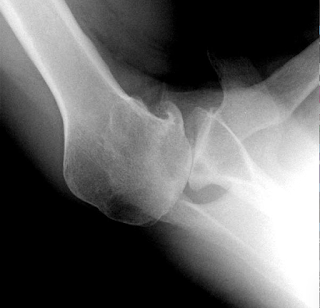

An AP x-ray in the plane of the scapula showed osteoarthritis with overlap of the humeral and glenoid articular surfaces.